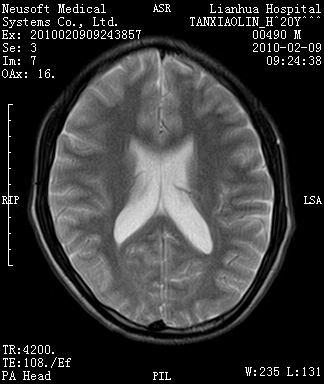

20岁男性患者,平时偶有头痛而无其他不适,现因持续头痛服药后无缓解而来院就诊。

松果体区占位继发轻度脑积水?该患者有ct资料,我已发上。

考虑松果体囊肿。

松果体囊肿?